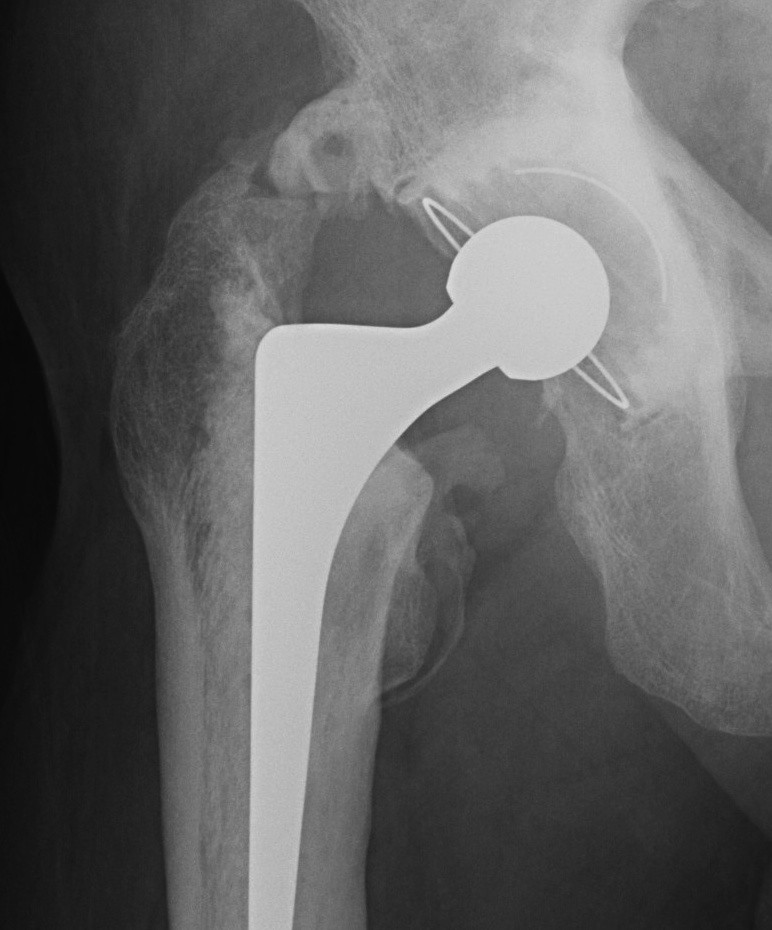

Оссификация тазобедренных суставов: что это и как проявляется?

Раздел: Сокровищница опыта